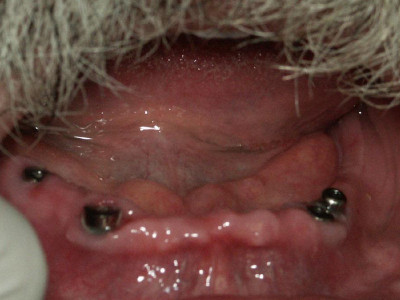

Terminado de Prótesis Hibridas superior e inferior atornillada sobre implantes que van fijas y no se las tiene que quitar el paciente